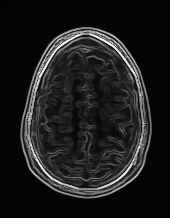

Edge preserving has always been a crucial concern in the design of reconstruction models. To improve the quality of reconstructed images and preserve image edges, some works suggested introducing edge priors in the original restoration problem to preserve image edges [4, 34]. However, they will suffer from complicated algorithm design and time-consuming training processes. Recently, some more efficient methods have been proposed to use edge maps as external guidance for image restoration. For example, Yang et al. [48] used off-the-shelf edge detectors to extract image edges from the degraded images. Fang et al. [12] predicted image edges by constructing an edge reconstruction network. Huang et al. [18] designed a novel dual discriminator GAN framework for solving fast multi-channel MRI, in which one GAN network is built for edge information enhancement. Inspired by these methods, we also consider introducing image edge prior as external guidance to MRI reconstruction since 1) image edges are prominent and distinguishable features in MRI (see Fig. 1), which can serve as a good guide to the model to recover high-frequency details; 2) the ground truth edges can be easily fetched via ordinary edge extraction operators, like Canny, Sobel, and Prewitt, which means that the edge maps can be learned in a data-driven manner. However, how to effectively utilize image edge priors to guide image reconstruction still remains a challenge. In some methods, edge information was simply concatenated with the input image and passed to the next stages. Though this is a simple way to utilize the edge priors, it may not give full play to the guiding role of the edge priors. Therefore, in this work, we want to explore a more efficient and effective mechanism to fully take advantage of image edge priors.

(a)

(b)

(c)

fastMRI is a large-scale MR dataset jointly established by Facebook AI Research and NYU Langone Health. It provides both knee and brain datasets for evaluation. In our work, we use the multi-coil knee dataset, which was acquired on three clinical 3T systems or one clinical 1.5T system using a 15-channel knee coil array. The dataset includes data from two pulse sequences, yielding coronal proton-density weighting with (PDFS) and without (PD) fat suppression. As is shown in Fig. 1, PD images usually contain more structural and prominent edge features than PDFS images, which suggests that it is more challenging to use edge guidance on PDFS datasets. Therefore, we explore the effectiveness of EAMRI on these two modalities. Following [13], for both PD and PDFS knee datasets, we separately filter out 227 volumes (8332 slices) for training and 24 volumes (1665 slices) for testing. The dataset is centrally cropped to .